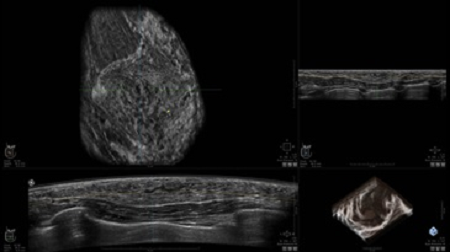

• Получение объемных 3D изображений с возможностью покадрового просмотра

Технические параметры рабочей станции

• Отображение объемных 3D ультразвуковых изображений, которые состоят из традиционных поперечных и воссозданных коронарных и сагиттальных проекций

• Возможность отображения полного 3D изображения

• Многооконный просмотр: 4 - 12 изображений

• Стандартизованная ориентация изображения: «толстый срез» в коронарной плоскости; поперечная; сагиттальная плоскость; радиальный и антирадиальный поворот изображения; просмотр исключительно области интереса

• Изменяемая толщина среза: 0,5 - 10,0 мм (шаг 0,5 мм)

• Срез: 0,5 - 2,0 мм (шаг 0,5 мм)

• 360 ° APC - отображение области по «любой точке компаса»

• Одновременный просмотр двух изображений для сопоставления в коронарной плоскости